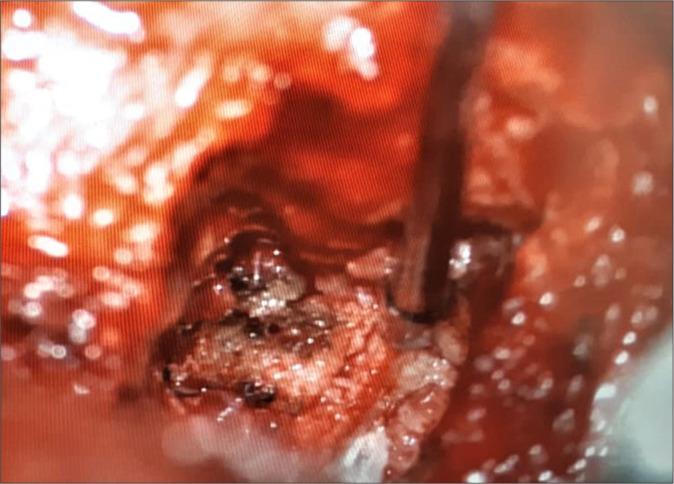

A 46-year-old female underwent a TLIF L3-L4. Five months later, she presented with cauda symptoms/signs of dorsal cage migration that warranted surgical removal.

一名46岁女性接受了L3-L4节段的TLIF手术。五个月后,她出现了融合器向后移位至椎管的马尾症状/体征,需要进行手术取出。